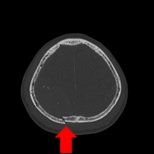

- 頭部

| 頭部領域のCTでは主に脳出血や脳梗塞などの脳の精査、頭部骨折などの骨の精査、耳鼻科領域の精査を目的とした撮影を行います。 | ||

| 単純頭部CT(脳出血) | 骨条件(骨折) | 3D画像(後頭部) |

| 外傷性脳出血+頭蓋骨骨折 | ||